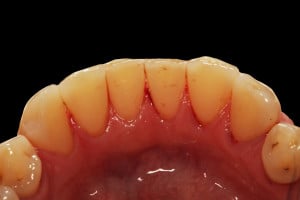

Wykonano higienizację jamy ustnej poprzez usunięcie kamienia nazębnego skalerem ultradżwiękowym, zdjęciem osadu i płytki nazębnej poprzez piaskowanie air flow plus oraz classic, a następnie wypolerowaniu gumką ze specjalistyczną pastą polerską: